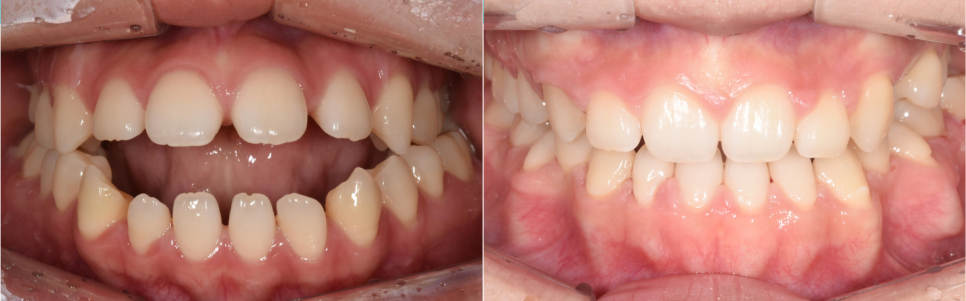

(좌) 어금니가 다물어져있는데도 앞니는 물리지 않고 떠 있다. (우)환자분 기준 "왼쪽"에는 어금니가 하나밖에 없다

2단계: 교합 개선(맞물림 조정)

위턱의 틀이 확보된 후에는 위아래 어금니가 올바르게 물리도록 세밀하게 조정합니다. 사실 이 단계까지만으로도 많은 변화가 일어납니다. 혀가 제 자리를 찾으면서 밀려 나갔던 앞니 공간이 상당 부분 개선되고, 비정상적으로 높게 물리던 교합이 안정되면서 육안으로 보이는 턱의 길이도 훨씬 짧아 보이게 됩니다.

치료 결과

이렇게 모든 치료가 끝났습니다. 환자분의 처음 고민이었던 세 가지 문제가 어떻게 개선 되었는지 다시 한 번 정리해보겠습니다.

앞니 개방교합의 해소

좁았던 입천장이 넓어지자 갈 곳 없던 혀가 자연스럽게 제자리를 찾게 되었습니다. 혀가 앞니를 밀어내던 힘이 사라지면서, 붕 떠 있던 앞니들이 비로소 정상적으로 맞물리기 시작했습니다. 이제는 음식물을 앞니로 편하게 끊어 드실 수 있게 되었고, 미소도 훨씬 예뻐졌습니다.

돌출입 증상의 개선

치아들이 배열될 충분한 공간이 확보되자, 앞으로 뻗어 있던 치아들이 제 위치로 들어갔습니다. 이 과정에서 입술 라인이 자연스럽게 뒤로 이동하며, 환자분이 원하셨던 세련되고 편안한 입매가 완성되었습니다.

안면 비대칭의 완화

양쪽 어금니의 교합 높이를 균일하게 맞추는 정밀한 조정 과정을 거쳤습니다. 특히 미니 스크류를 이용해 윗니를 살짝 압입시켜 우측 턱이 더 깊게 물리도록 유도한 결과, 골격적 한계가 있었음에도 불구하고 육안으로 보이는 얼굴 비대칭이 개선되었습니다.